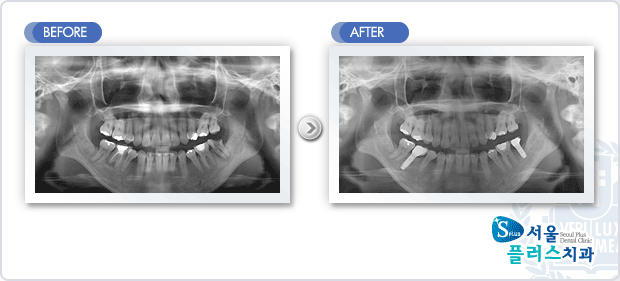

[임플란트] 임플란트 - 좌,우 구치부 뿌리끝 염증에 의한 발치후 임플란트 식립